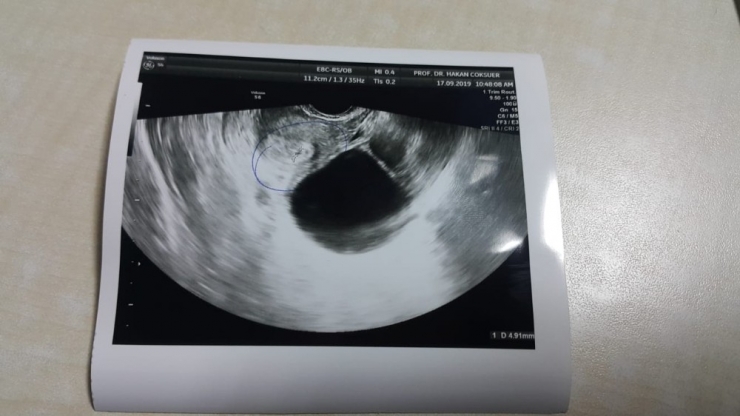

Almanya'da yaşayan Mülkiye İlhan Alp çifti, hayatlarını birleştirdikten sonra çocuk sahibi olamadı. Çocuk hasreti çeken çift, Almanya'da ve Avrupa'da birçok yere başvurdu. Çift başvurmadık klinik, gitmedik doktor bırakmadı. Arkadaş tavsiyesi üzerine Diyarbakır'da Kadın Doğum ve Tüp Bebek Uzmanı Prof. Dr. Hakan Çoksüer önerisi alan Alp çifti yaptıkları araştırmalar sonucu Diyarbakır'a gelerek klinikte tedavi süreci başlattı. Hem erkek hem de kadın faktöründen kaynaklı rahatsızlığa yapılan sperm detoksu ve akupunktur tedavisiyle gebelik kesesini gören Alp ailesinin hasreti son buldu.

Spermi genetik olarak ayıklama metodunu başarıda önemli bir anahtar olarak gördüklerini ifade eden Dr. Çoksüer, "Ama asıl önemli olan şey, sperm detoks tedavisi ve aynı zamanda akupunktur tedavisi. Uygun hastalarda uygun tedavilerle başlamak bizim için önemli. Biz burada sevindiren nokta hastanın Almanya'dan gelerek onları mahcup etmemek bizim için müthiş bir mutluluk kaynağı. Hasta kliniğimize geldiğinde, Avrupa'nın birçok kentinde kliniğe başvurduğunu söyledi. Birçok kentte tedavi aldığını söyledi. Hiçbir şekilde tedaviye başarıya ulaşamadıklarını dile getirdiler. Yaptığımız araştırmalar ve tedaviler sonucunda hastamızın süreci gebelikle sonuçlandı. Gebelik kesesi görüldükten sonra ailede müthiş bir mutluluk yaşandı, mutluluk çığlığı atıldı. Rabbim çocuk sahibi olmak isteyen herkese bu mutluluğu yaşatsın inşallah. Çocuk sahibi olamayanlar lütfen hiçbir şekilde motivasyonları, umutlarını yitirmesinler. Sadece her zaman doğru arayışta, doğru yerde, doğru hekimde tedavi olmalarını öneriyorum" şeklinde konuştu.